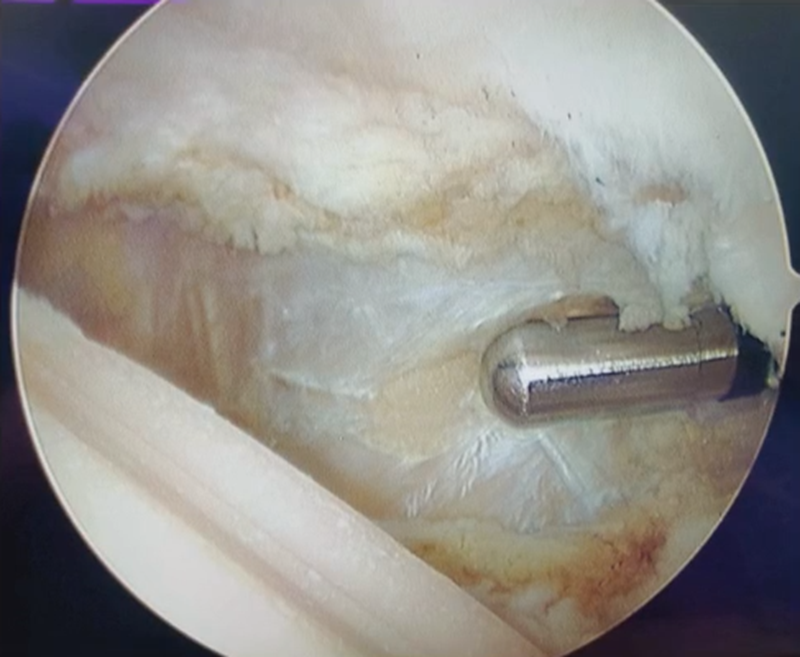

结合影像学检查,该患者不适合做关节置换,最终选择关节镜探查后,切开行髌骨成形术。

外侧入路切开,打开关节囊,术中可见大量骨赘,用咬骨钳去除。骨赘去除后,原来的Wiberg Ⅲ型髌骨恢复变为Wiberg Ⅱ型髌骨。

外侧支持韧带松解